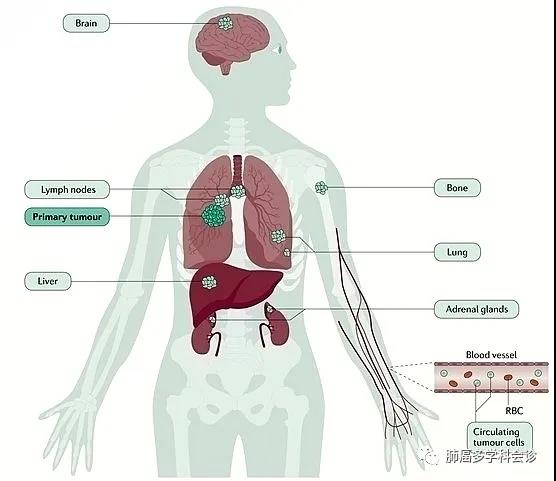

肺癌扩散转移速度到底有多块?小细胞肺癌扩散最快,腺癌次之...

肺癌扩散转移速度到底有多块?小细胞肺癌扩散最快,腺癌次之...

破解吸烟促进肺癌细胞脑转移之谜!科学家发现尼古丁能改变小胶质细...

破解吸烟促进肺癌细胞脑转移之谜!科学家发现尼古丁能改变小胶质细...

谁对肺癌脑转移效果更胜一筹?全脑放疗还是立体定向放射治疗?...

谁对肺癌脑转移效果更胜一筹?全脑放疗还是立体定向放射治疗?...

肺癌骨转移:护骨和治疗都重要!

肺癌骨转移:护骨和治疗都重要!

最全“肺癌脑转移”全面解读,延长生存期的要点...

最全“肺癌脑转移”全面解读,延长生存期的要点...

关于肺癌转移的九大误区,不论医生还是患者都可能有过...

关于肺癌转移的九大误区,不论医生还是患者都可能有过...